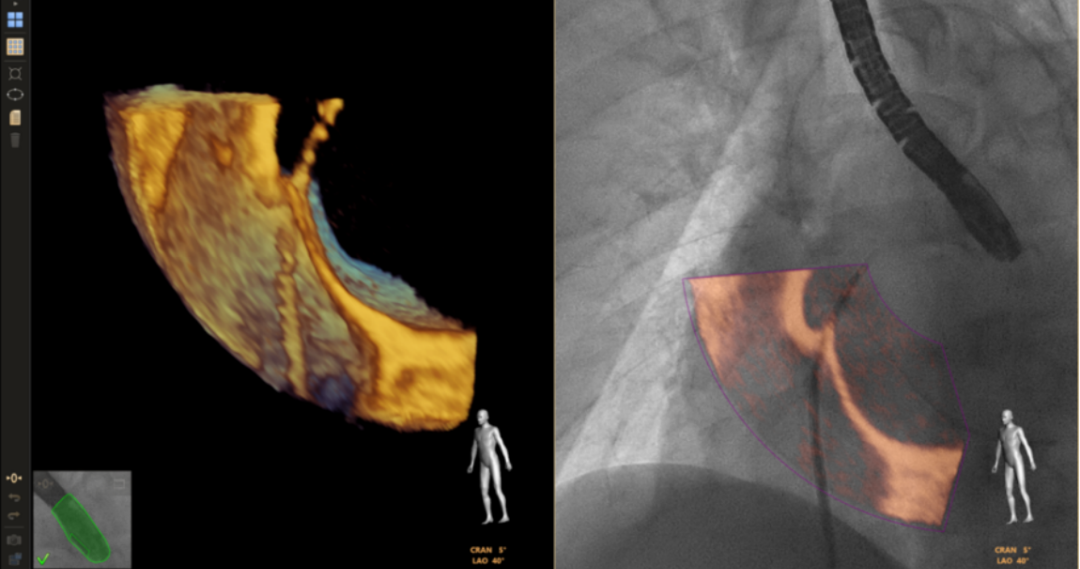

Echo Navigator是飞利浦推出的创新影像融合技术,专为心脏介入手术设计。它通过将实时超声图像与血管机图像相结合,辅助医生在进行经导管左心耳封堵术(LAAC)、二尖瓣缘对缘修复术、三尖瓣植入术、主动脉瓣置换术(TAVR)及瓣周漏修复等复杂手术时,实现更精准的导航。该技术显著提升了手术的安全性和效率,为医生提供了前所未有的视觉辅助,优化了患者治疗结果。

下面是Echo Navigator的几个经典临床应用场景

2、二尖瓣缘对缘修复术TEER:TEER技术自问世以来,经过不断的研发和改进,已成为治疗二尖瓣反流的重要手段之一。TEER手术需要在超声引导下进行, Echo navigator的功能在于将DSA图像与超声图像巧妙融合,在TEER手术中,它如同为手术医生和超声医生配备了一副“透视心脏结构的超级眼镜”。这种融合技术不仅让手术医生能实时洞察血管的精准位置与形态,还结合超声图像揭示的组织结构与心脏活动细节,极大地增强了手术的精准度与安全性。超声医生则能借此全面把握手术区域的血流动态,为手术决策提供宝贵依据。总之,这一功能极大地提升了手术团队的合作效率与手术质量,为患者带来更加安全、有效的治疗体验。

点击查看大图

无论是TEER还是LAAO房间隔结构的实时呈现都非常重要,Echo Navigator提供的增强解剖模型和自动化解剖洞察功能,就像是探险队手中的强光手电筒和探测器,帮助医生们快速、准确地找到目标区域。而自动MPR(多平面重建)平面和同时可以实时匹配DSA图像和超声图像的Mark标注,则进一步简化了手术医生获取最佳临床视野的过程,使得手术操作更加得心应手。